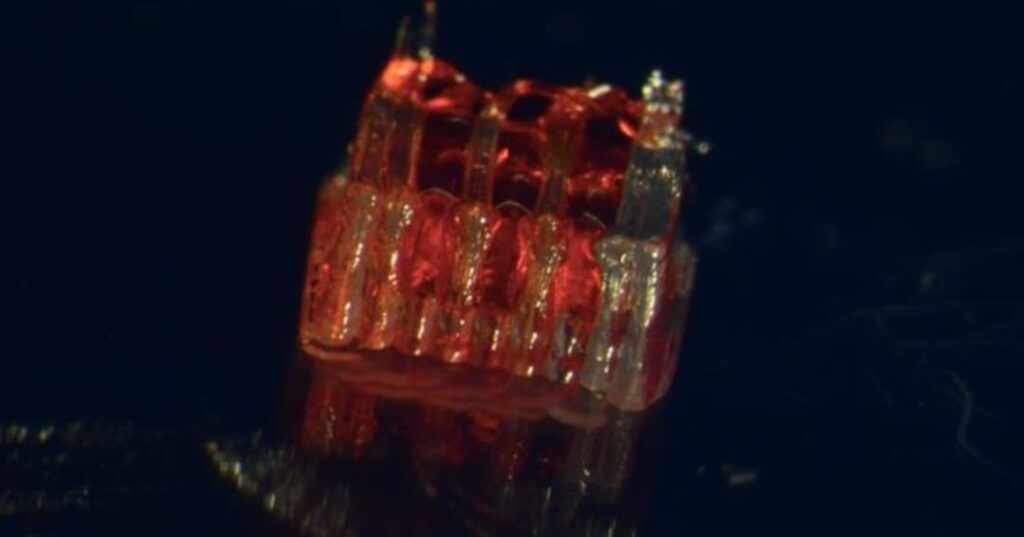

El equipo desarrolló una estructura innovadora impresa en 3D para órganos cultivados en laboratorio, llamada andamio organoidal, que contiene canales microscópicos.

Capturas del estudio. Clic para ampliar.